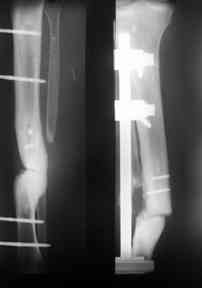

Больной 33 года поступил в отделене с открытой травмой голени на фоне тугого ложного сустава. Первичная травма более десяти лет назад открытый перелом костей , перенес 8 операций по поводу несростающегося перелома голени и далее травматического остеомиелита и ложного сустава, Последние 2 года ходил с полной нагрузкой на конечность без ортопедического тутора, отмечал некоторую болезненность при значительных нагрузках. В результате падения получил травму голени, резкую потерю опороспособности, наличие раны по наружной поверхности голени в виде лучей 3х10х 4х8 см.Дном раны является кость. Кожа представляет из себя рубцы, которые "взорвались" при воздейстии на них отломков, вернее концов ложного сустава. Даже диагноз сложно сформулировать, скорее открытый ложный сустав 2-3типа. Первично срержневой аппарат,аддаптирующие швы на кожные лоскуты,сохраняется дефект кожи 4х6 см, да и на окружающие кожно -рубцовые ткани надежд нет, намечается некроз.Учитывая бесполезность сращения склерозированных концов ( а это доказано 10 летними попытками), а также значительный дефект кожи планируем произвести резекцию концов ( планируемый дефект 6-7 см), далее ЧКДО на укорочение, контатк отломков сращение с последующим восстновлением длинны за счет остетомии и транспорта в в/3 голени- это в стандарной ситуации. Есть идея совместить штифт и аппарат.Важны Ваши мнения и совет ув. коллеги!

Планируем резекцию склерозированных концов, вскрытие каналов, введение штифта без дистального блокирования и дозированное (в течении 5-7 дней) укорочение на 2 кольцах, что позволит нам закрыть рану. Далее возможны 2- варианта 1 после заживление раны остетомия в в\3 и транспорт на штифте, либо 2 отсрочить эти мероприятия и просто выполнить дистальное блокирование, динамизация и снятие аппарата, восстановление длинны оставить на будущее. Опороспособность взамен на длинну.

Вторым этапом можно приступить к восстановлению на кости, это может быть сделано аппаратом Илизарова с иссечением концов костей с дальнейшими удлинениями или доступными интра, экстра-медуллярными методами. У нас тоже похожий случай, коллега пластический хирург помог мне, больной после 13 операций на голени,

инфицированный с металлоконструкцией ложный сустав

ангиография,

взятие вены сафенус и подключение к popliteal artery,

rectus muscular flap

вид в аппарате

и окончательный вид.